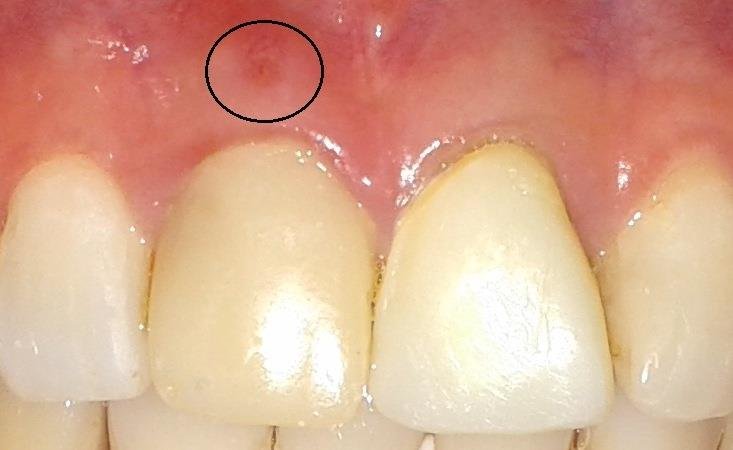

Have you ever noticed a small pimple-like bump on your gum that sometimes drains pus or comes and goes?

This is often a sinus tract, also known as a dental fistula. It is your body’s way of dealing with an infection inside a tooth. A sinus tract is not the infection itself, it’s simply a drainage pathway. The real problem lies inside the tooth.

- A small bump on the gum near a tooth

- Sometimes the bump drains fluid or pus

- It may not hurt (because it’s draining!)